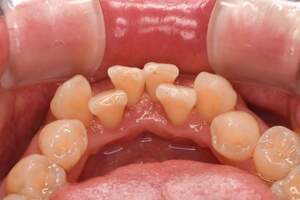

歯石除去

治療前

治療後

| 年齢 | 40歳・男性 |

| 主訴 | 歯石をとりたい |

| 治療内容 | 歯石除去 |

| 治療期間 | 30分 |

| 費用 | 約2,000円 |

| リスク・副作用 | ・歯ぐきの炎症が強いと歯石を取る際に出血することがあります。 ・処置後に歯がしみることがあります。 ・歯と歯の間に隙間ができるので、息が漏れ発音しにくいと感じることがあります。 ・歯ぐきの炎症が軽減すると歯ぐきが引き締まり、歯が長く見えることがあります。 |